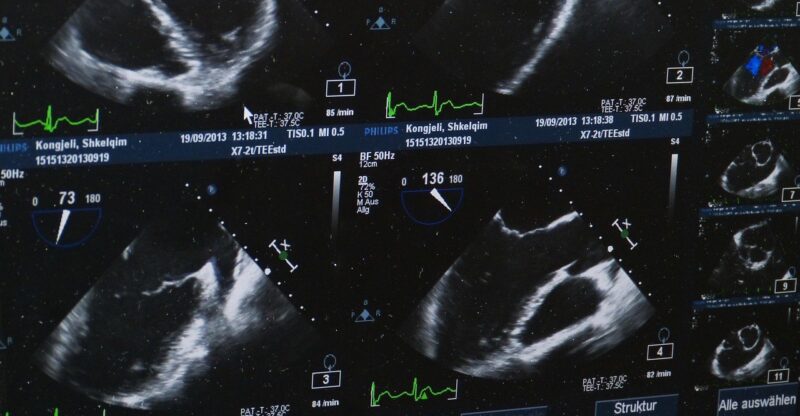

USG opiera się na technologii fal ultradźwiękowych, które są bezpieczne dla organizmu i nie powodują skutków ubocznych. Głowica aparatu wysyła fale, które odbijają się od narządów wewnętrznych, a następnie komputer przekształca odbite sygnały w realistyczny obraz na monitorze. W ten sposób możliwe jest zobaczenie kształtu, wielkości czy struktury tkanek w czasie rzeczywistym.

Ultrasonografia znajduje zastosowanie w ocenie narządów takich jak wątroba, nerki, trzustka, tarczyca, a także naczyń krwionośnych czy narządów kobiecych. Dzięki dodatkowemu trybowi dopplerowskiemu możliwe jest również śledzenie przepływu krwi – ma to ogromne znaczenie np. w diagnostyce powikłań cukrzycy. To badanie nie wymaga użycia kontrastów ani wcześniejszej hospitalizacji, co znacząco zwiększa jego dostępność i komfort dla pacjenta.